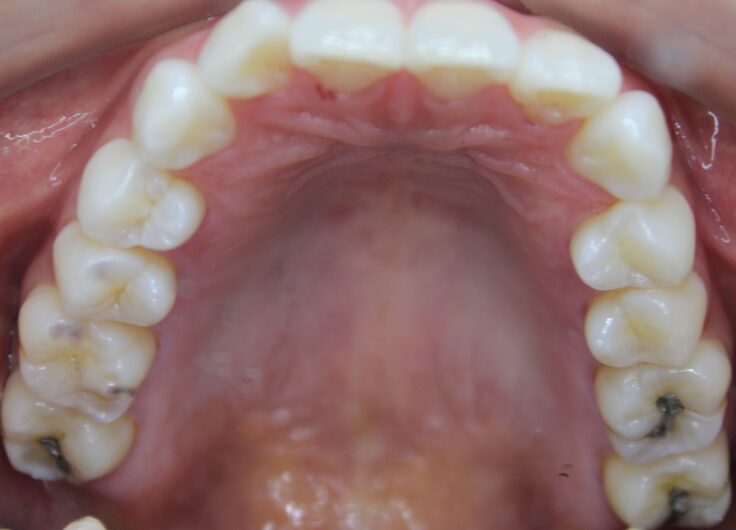

こんにちは。歯科衛生士の川西です。 今までは保険で歯周病治療に来院されていた患者様が ご自身の口腔内に不安をもたれて…